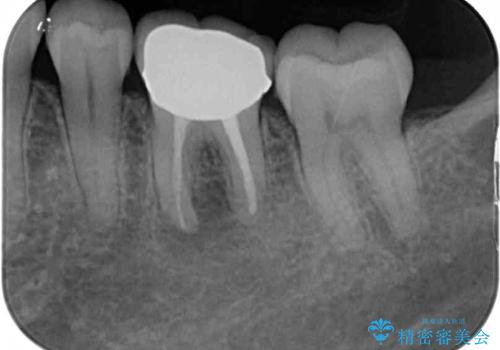

処置後、下顎の膿の出口はすぐに消えましたが、レントゲン写真からも分かるとおり、歯根途中に穴が開いており、充填材が歯根外にはみ出していました。数ヶ月経過を見たところ、特に異常は認められなかったため、補綴治療を行いました。